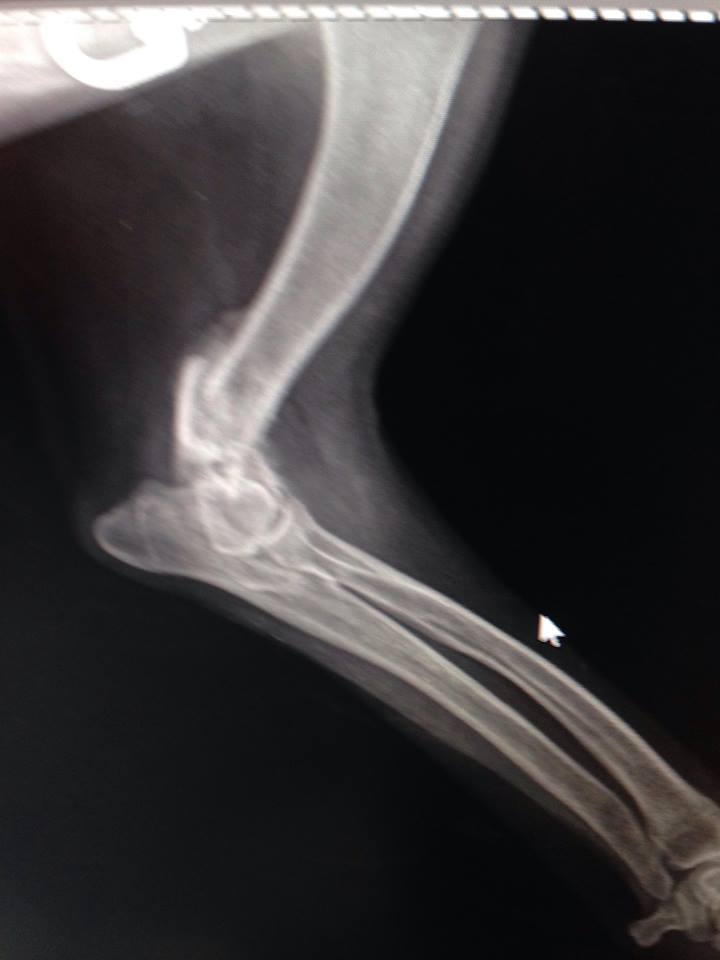

Вобщем все гораздо хуже оказалось.Только характер приятный,ласкавая.

Очень паршивый перелом.... сложная операция.

Не понятно куда и зачем одевали гипс.... зато стерилизовали.